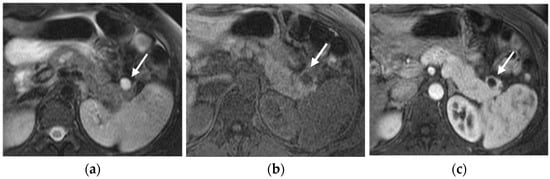

MRI

Contrast-enhanced MRI allows the detection of pNETs with higher sensitivity (65–85%) compared to contrast-enhanced CT.

The specific MRI appearance of PNETs can be influenced by factors such as tumor grade, size, and the presence of cystic or necrotic areas within the lesion [40] (Figure 5).

Figure 5.

Cystic pancreatic NET of the tail (arrows). Fat-sat T2-weighted image (a) and T1-weighted image (b) show a cystic-like lesion in the pancreatic tail with a thick and irregular enhancing wall (c,d). PET-CT highlights high tracer uptake of the lesion (e). In the same patient, ultrasound revealed a synchronous parathyroid adenoma (f).

Compared to the surrounding pancreatic tissue, pNETs usually appear isointense/hypointense on T1-weighted MRI sequences and variably hyperintense on T2-weighted MRI sequences, depending on the amount of collagen in the tumor [32].

PNETs exhibit varying signal intensity with Diffusion-Weighted Imaging (DWI), but they often demonstrate restricted diffusion, with smaller lesions potentially being not easily detected on other MRI sequences [17]. Less differentiated tumors demonstrate even more diffusion restriction (Figure 6).